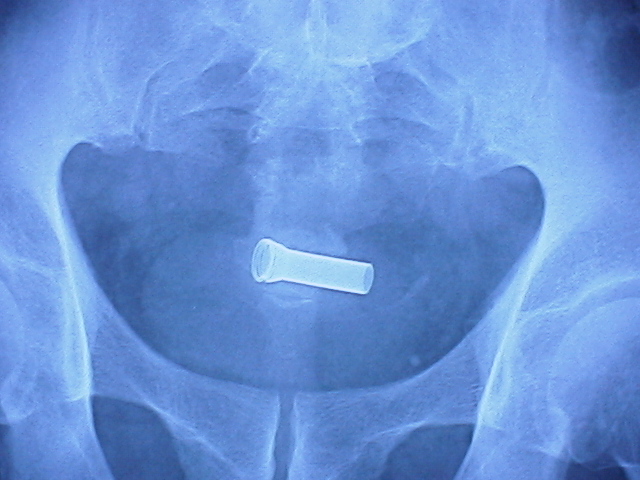

前立腺部尿道に留置したはずのコイルが、

膀胱内に落っこちる、というのはよくある話でした。